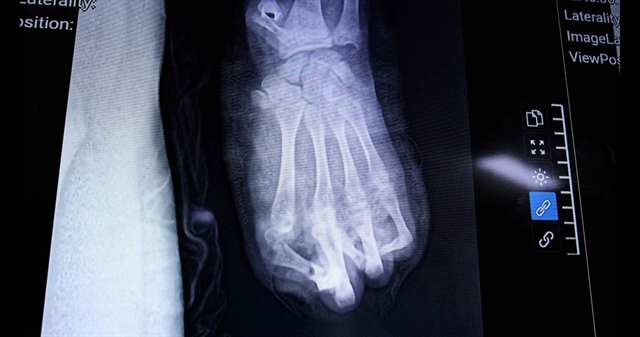

하노이(Hà Nội)에서 폭죽 폭발로 15세 소년의 왼손이 거의 완전히 파괴돼 108 중앙군병원(108 Central Military Hospital)에서 응급수술을 받았으나 손가락 2개만 보존되었다.

응급상처처치와 긴급수술을 진행한 상지수술·미세수술과 의료진은 응우옌 꽝 빈(Nguyễn Quang Vịnh) 박사의 진단 아래 환자의 손에서 다섯 손가락 중 두 개만 보존할 수 있었다.

손바닥과 손목 부위가 심각하게 손상되어 치료가 장기화될 것으로 보이며 향후 피부 피판 수술과 발가락을 엄지로 옮기는 수술 등이 계획되어 있다.